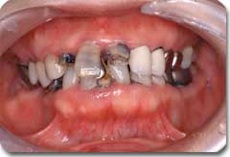

かみ合わせ治療前の状態です

かみ合わせ治療によりここまで治すことができます